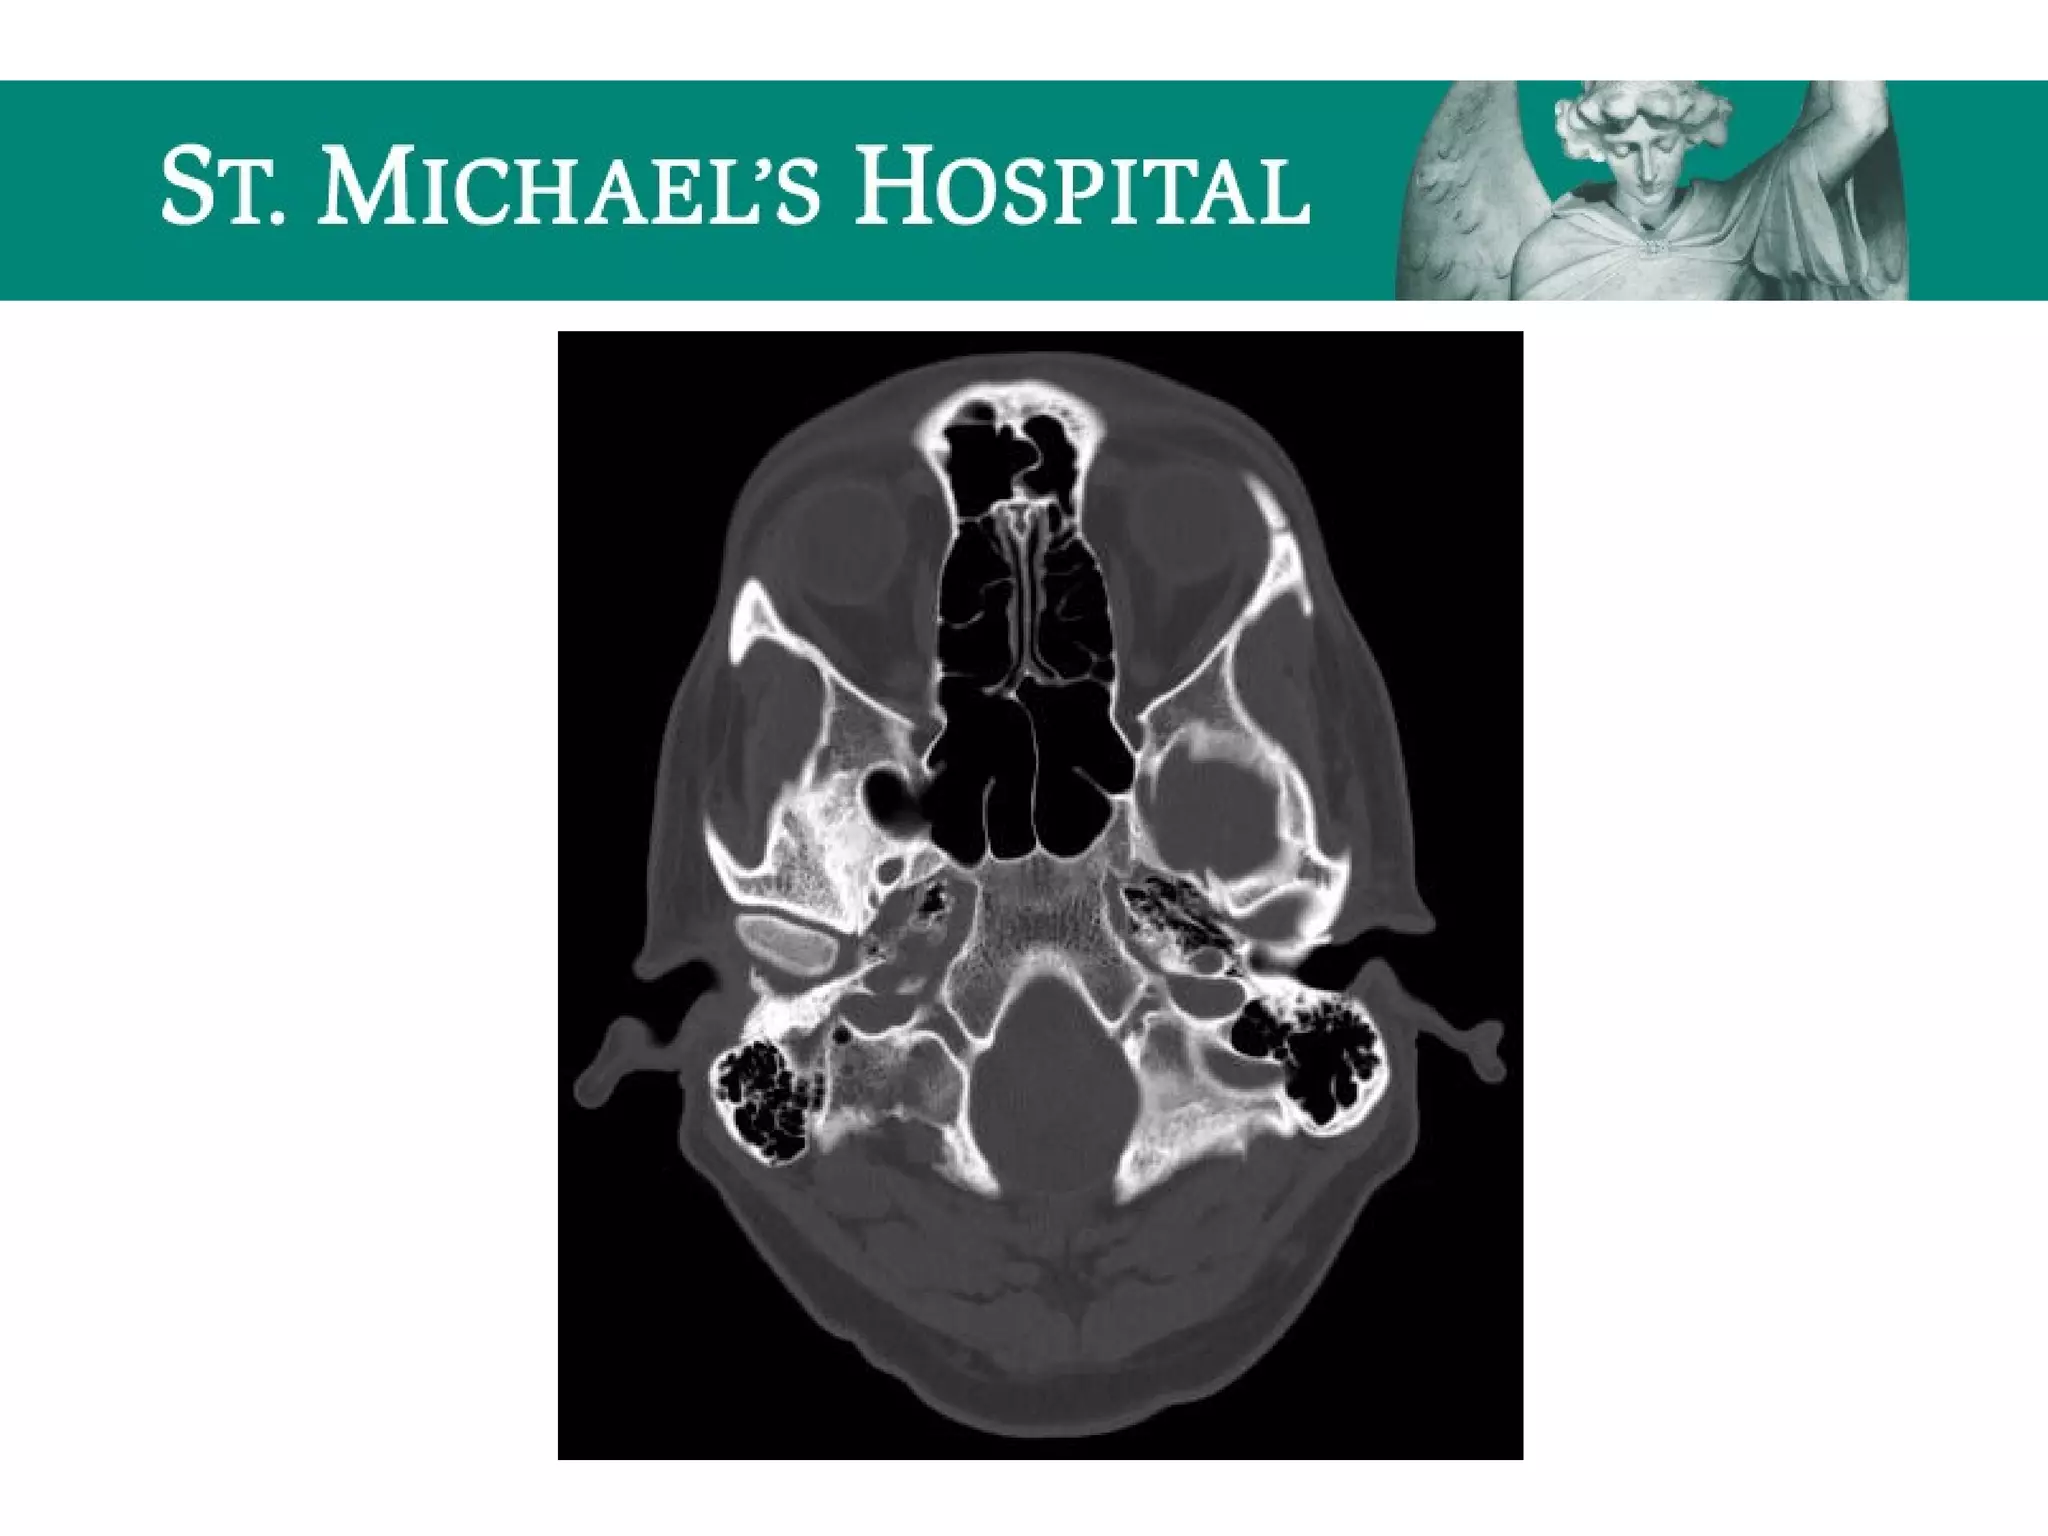

Unenhanced CT – Bone Window

 Paranasal sinuses

 Frontal, ethmoid, maxillary, sphenoid opacification

 Subcutaneous/orbital emphysema/pneumocephalus

 Mastoid air cells

 Opacification

 Hemotympanum

 Subcutaneous emphysema/pneumocephalus

 Bones (fractures)

 Facial  nasal bone, bony orbit, bony sinuses, mandible

 Skull base  petrous temporal bone fractures (longitudinal vs. transverse)

 Calvarium  linear vs. depressed

 Occipital condyles